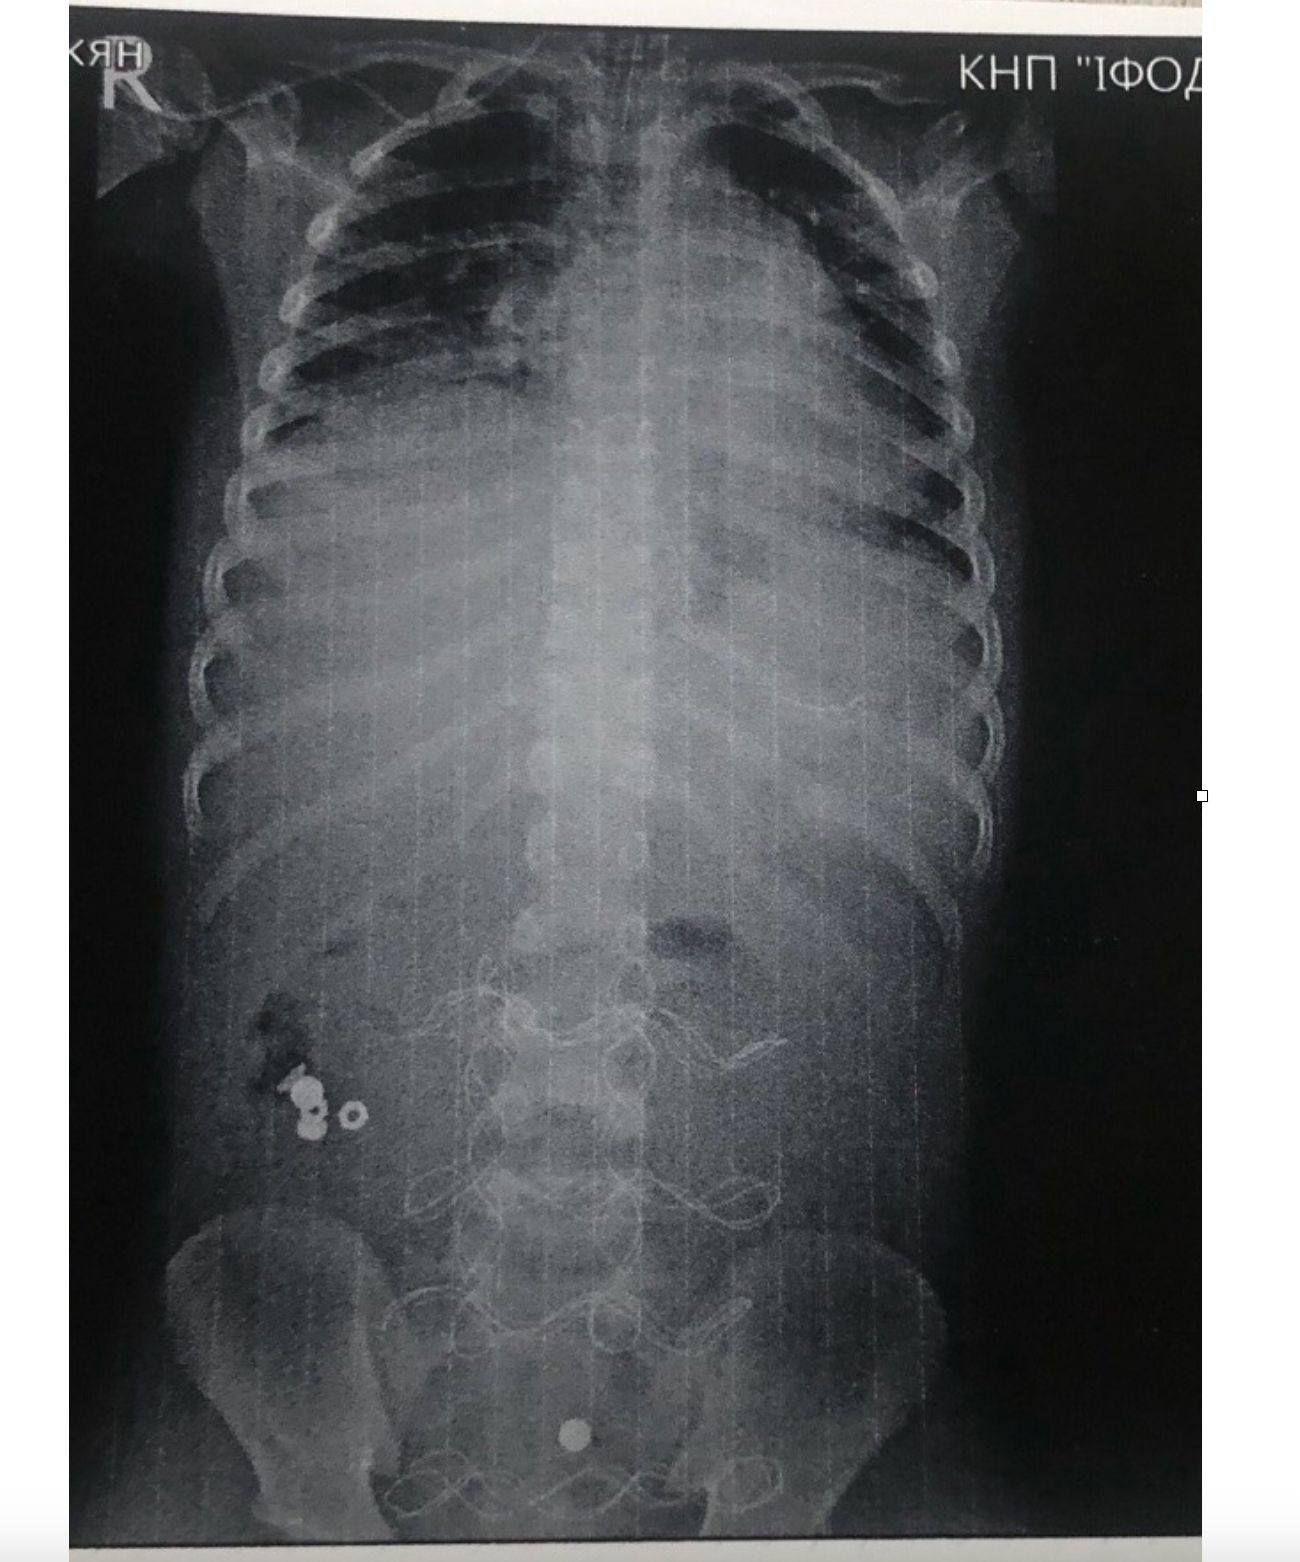

У Івано-Франківській обласній дитячій клінічній лікарні медики врятували 7-річного хлопчика, який потрапив у вкрай тяжкому стані через проковтнуту батарейку, що спричинила перфорацію кишківника та інфекційно-токсичний шок.

За його словами, до лікарні 7-річного хлопчика привезли у вкрай тяжкому стані: у нього діагностували інфекційно-токсичний шок та клініку розлитого перитоніту. Причиною серйозного стану виявилася проковтнута батарейка, яка спричинила перфорацію тонкого кишківника.

Передопераційна підготовка тривала понад 12 годин. Всього дитині провели три складні операації. Завдяки злагодженій роботі медиків, на 20-ту добу хлопчик був виписаний у задовільному стані.